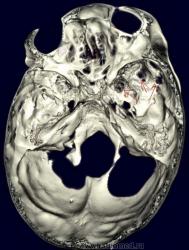

Метастазы в костях основания черепа.

Женщина средних лет с клиникой невралгии тройничного нерва справа. На КТ были выявлены округлые очаги деструкции в костях основания черепа (средней черепной ямки).

Наблюдение Nela.